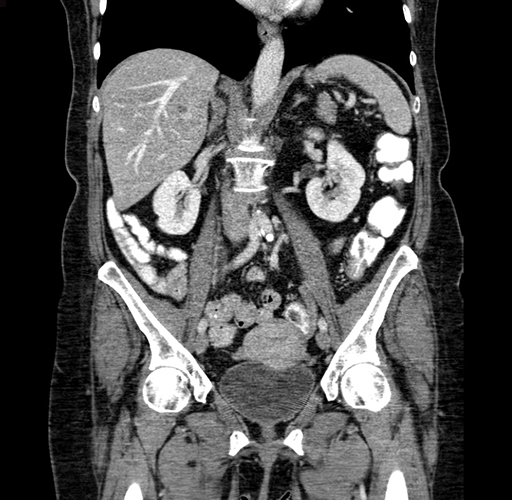

Pre-Chemo: Coronal Venous